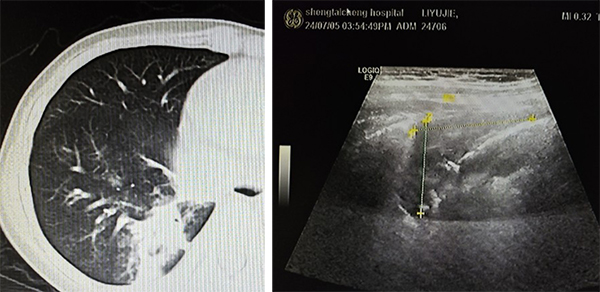

CT与超声均可见肺实变且范围一致